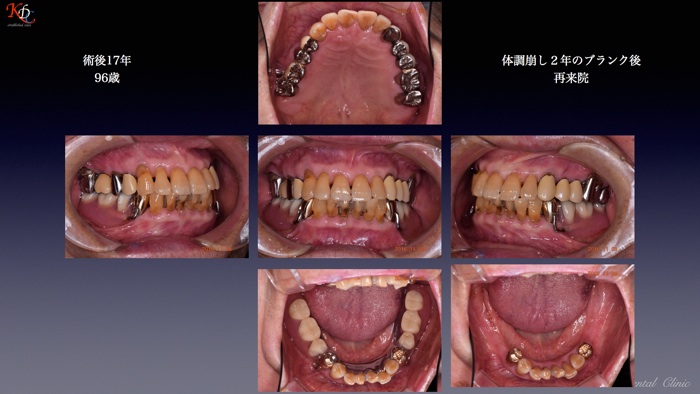

治 療例 1